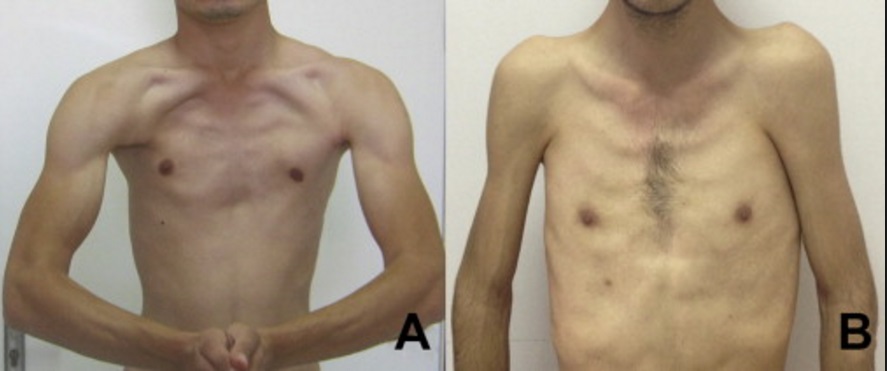

Deformity Of The Chest Wall: What Is Poland Syndrome? – Kimdeyir

kimdeyir.comWhat Is The Life Expectancy Of Someone With Poland Syndrome?

kimdeyir.comWhat Is The Life Expectancy Of Someone With Poland Syndrome?